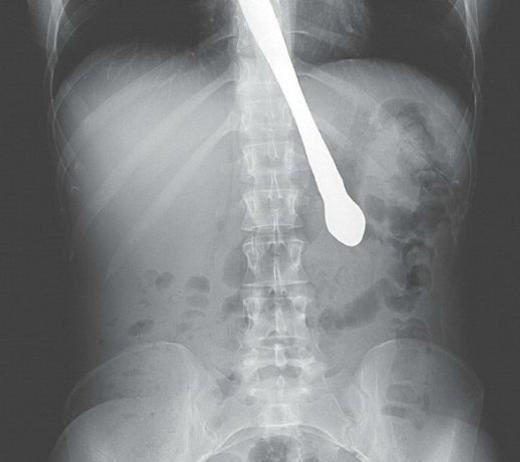

1. <p>Kimileri doktor hatası, kimileri de kaza... Huffington Post, dünyanın en garip tıbbi görüntülerini bir araya getirdi.</p>    Bu görüntü, Fransa'nın Lyon kentinde yaşayan Anne isimli bir kadına ait. Genç kadın, geçirdiği ameliyatın ardından bir türlü karın ağrılarından kurtulamayınca, doktorların rahminde ameliyat makası unuttuğu ortaya çıktı. Hatta o makas, kadının göbeğini deldi.

Bu görüntü, Fransa'nın Lyon kentinde yaşayan Anne isimli bir kadına ait. Genç kadın, geçirdiği ameliyatın ardından bir türlü karın ağrılarından kurtulamayınca, doktorların rahminde ameliyat makası unuttuğu ortaya çıktı. Hatta o makas, kadının göbeğini deldi.